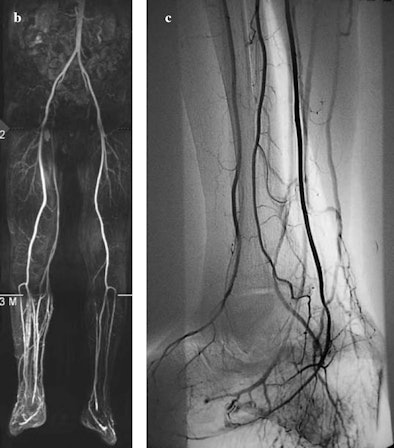

In addition, inflammatory hyperaemia caused by the ulcer can deteriorate the diagnostic quality of 40% to 50% of MR angiography studies in the infrapopliteal region. If and when that occurs, the researchers recommend selective arteriography.

| The images show osteomyelitis of the calcaneus due to infected neuropathic ulcer of the heel. In (a), the sagittal short-tau inversion-recovery sequence image shows a pathological fracture of the calcaneus and dislocation of the proximal fragment due to retraction of the Achilles tendon. In (b), MR angiography of the right lower limb is hindered by venous contamination in the distal third, whereas the left infrapopliteal arteries are clearly visible up to the plantar arch. In (c), selective arteriography of the right lower limb shows normal infrapopliteal arteries and early venous filling due to inflammatory hyperaemia. Images courtesy of La Radiologia Medica and Carlo Poma Hospital, Mantua, Italy. |